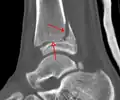

A triplane fracture of the ankle as seen on plain X-ray -

A triplane fracture of the ankle as seen on CT -

A triplane fracture of the ankle as seen on CT